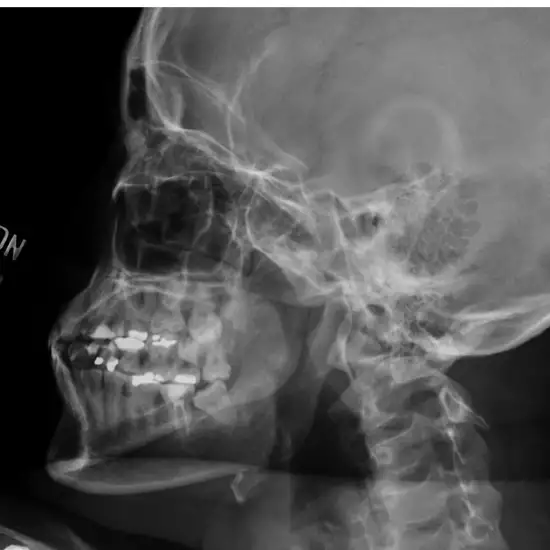

An X-ray of the TM Joints on the right side of the skull is helpful in seeing the two joints that link the jawbone to the skull (brainbox).

Why is it done?

To identify synovitis, capsulitis, and myositis (inflammation of the muscle connected to the TM joints)

• To identify temporomandibular (TM) joint injuries and jaw popping (displaced disc in the jaw)

• To diagnose malocclusion (sensation of teeth not meeting together)

• To identify TM joint discomfort, osteoarthritis, and osteoarthrosis (degeneration of the articular cartilage)

• To determine internal TMJ disturbance due to calcium deposition